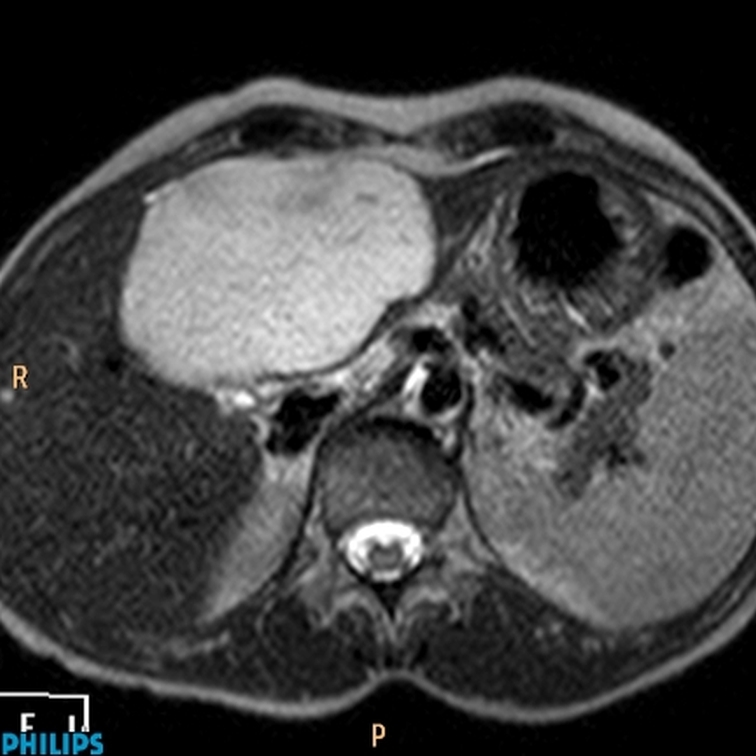

Light bulb sign

Hemangioma - appears very T2 bright